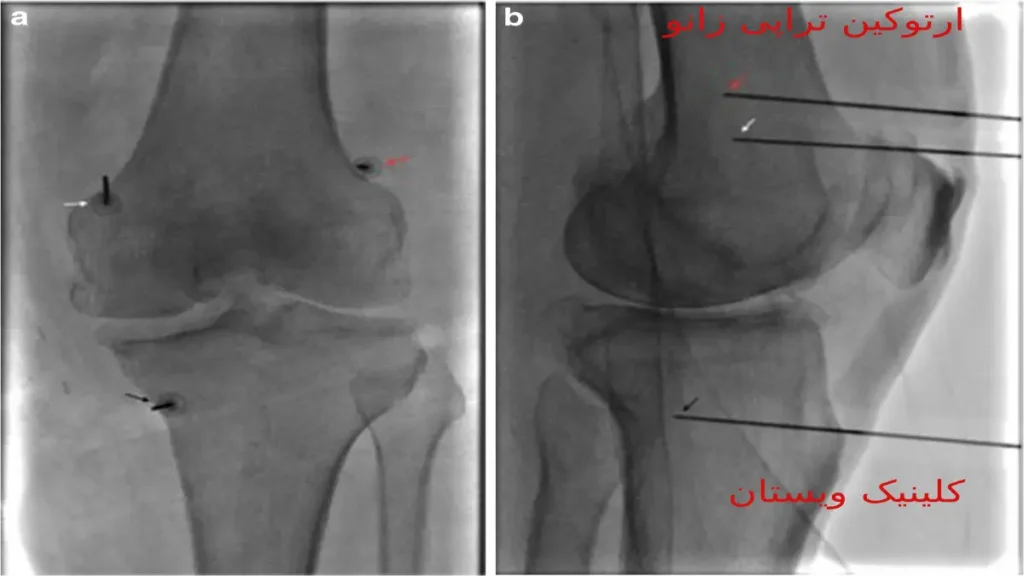

کلینیک ویستان، به مدیریت دکتر شهربانو کاظمی، یکی از مراکز ارائهدهنده ارتوکین تراپی در تهران است. برای اطلاع از هزینه دقیق و هماهنگیهای لازم، میتوانید با شماره تلفن ۰۹۱۲۳۹۶۸۲۷۰ تماس حاصل فرمایید.

کلینیک توانبخشی ویستان، به مدیریت دکتر شهربانو کاظمی، در تهران واقع شده و خدمات متنوعی در زمینه طب فیزیکی و توانبخشی ارائه میدهد.

آدرس کلینیک: اتوبان اشرفی اصفهانی – بلوار مرزداران – بعد از خیابان رضایی نژاد و بهار – پلاک ۱۸۴ – ساختمان ایمان – طبقه همکف شرقی (پشت داروخانه دکتر ختمی). شماره تماس: ۰۲۱۴۴۳۸۷۷۸۵.